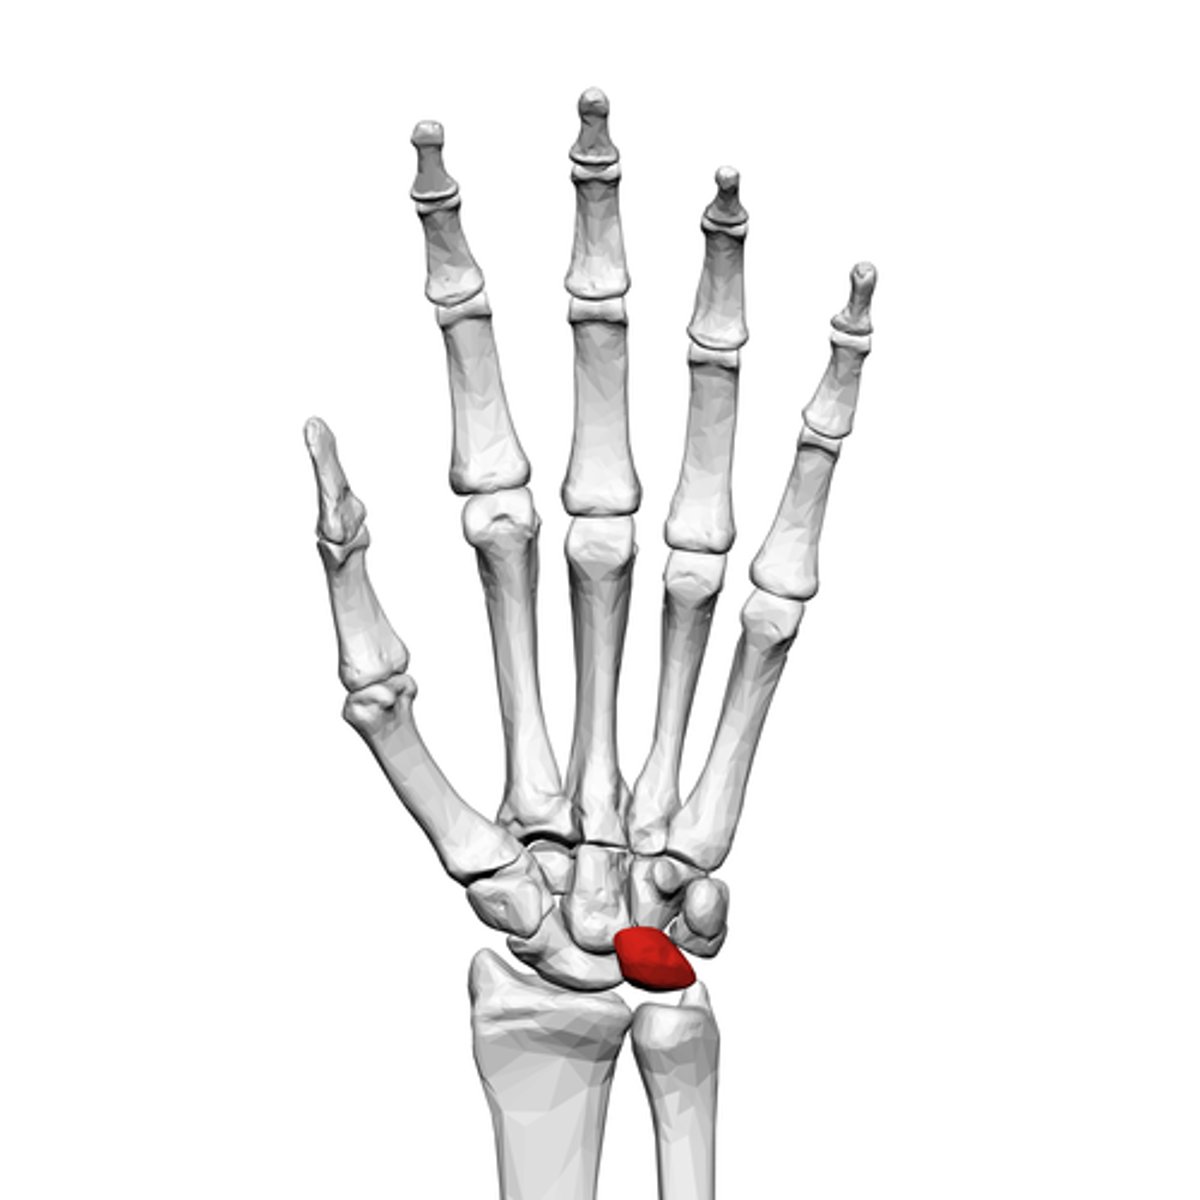

What is the term of the bones highlighted in red?

Triquetrum